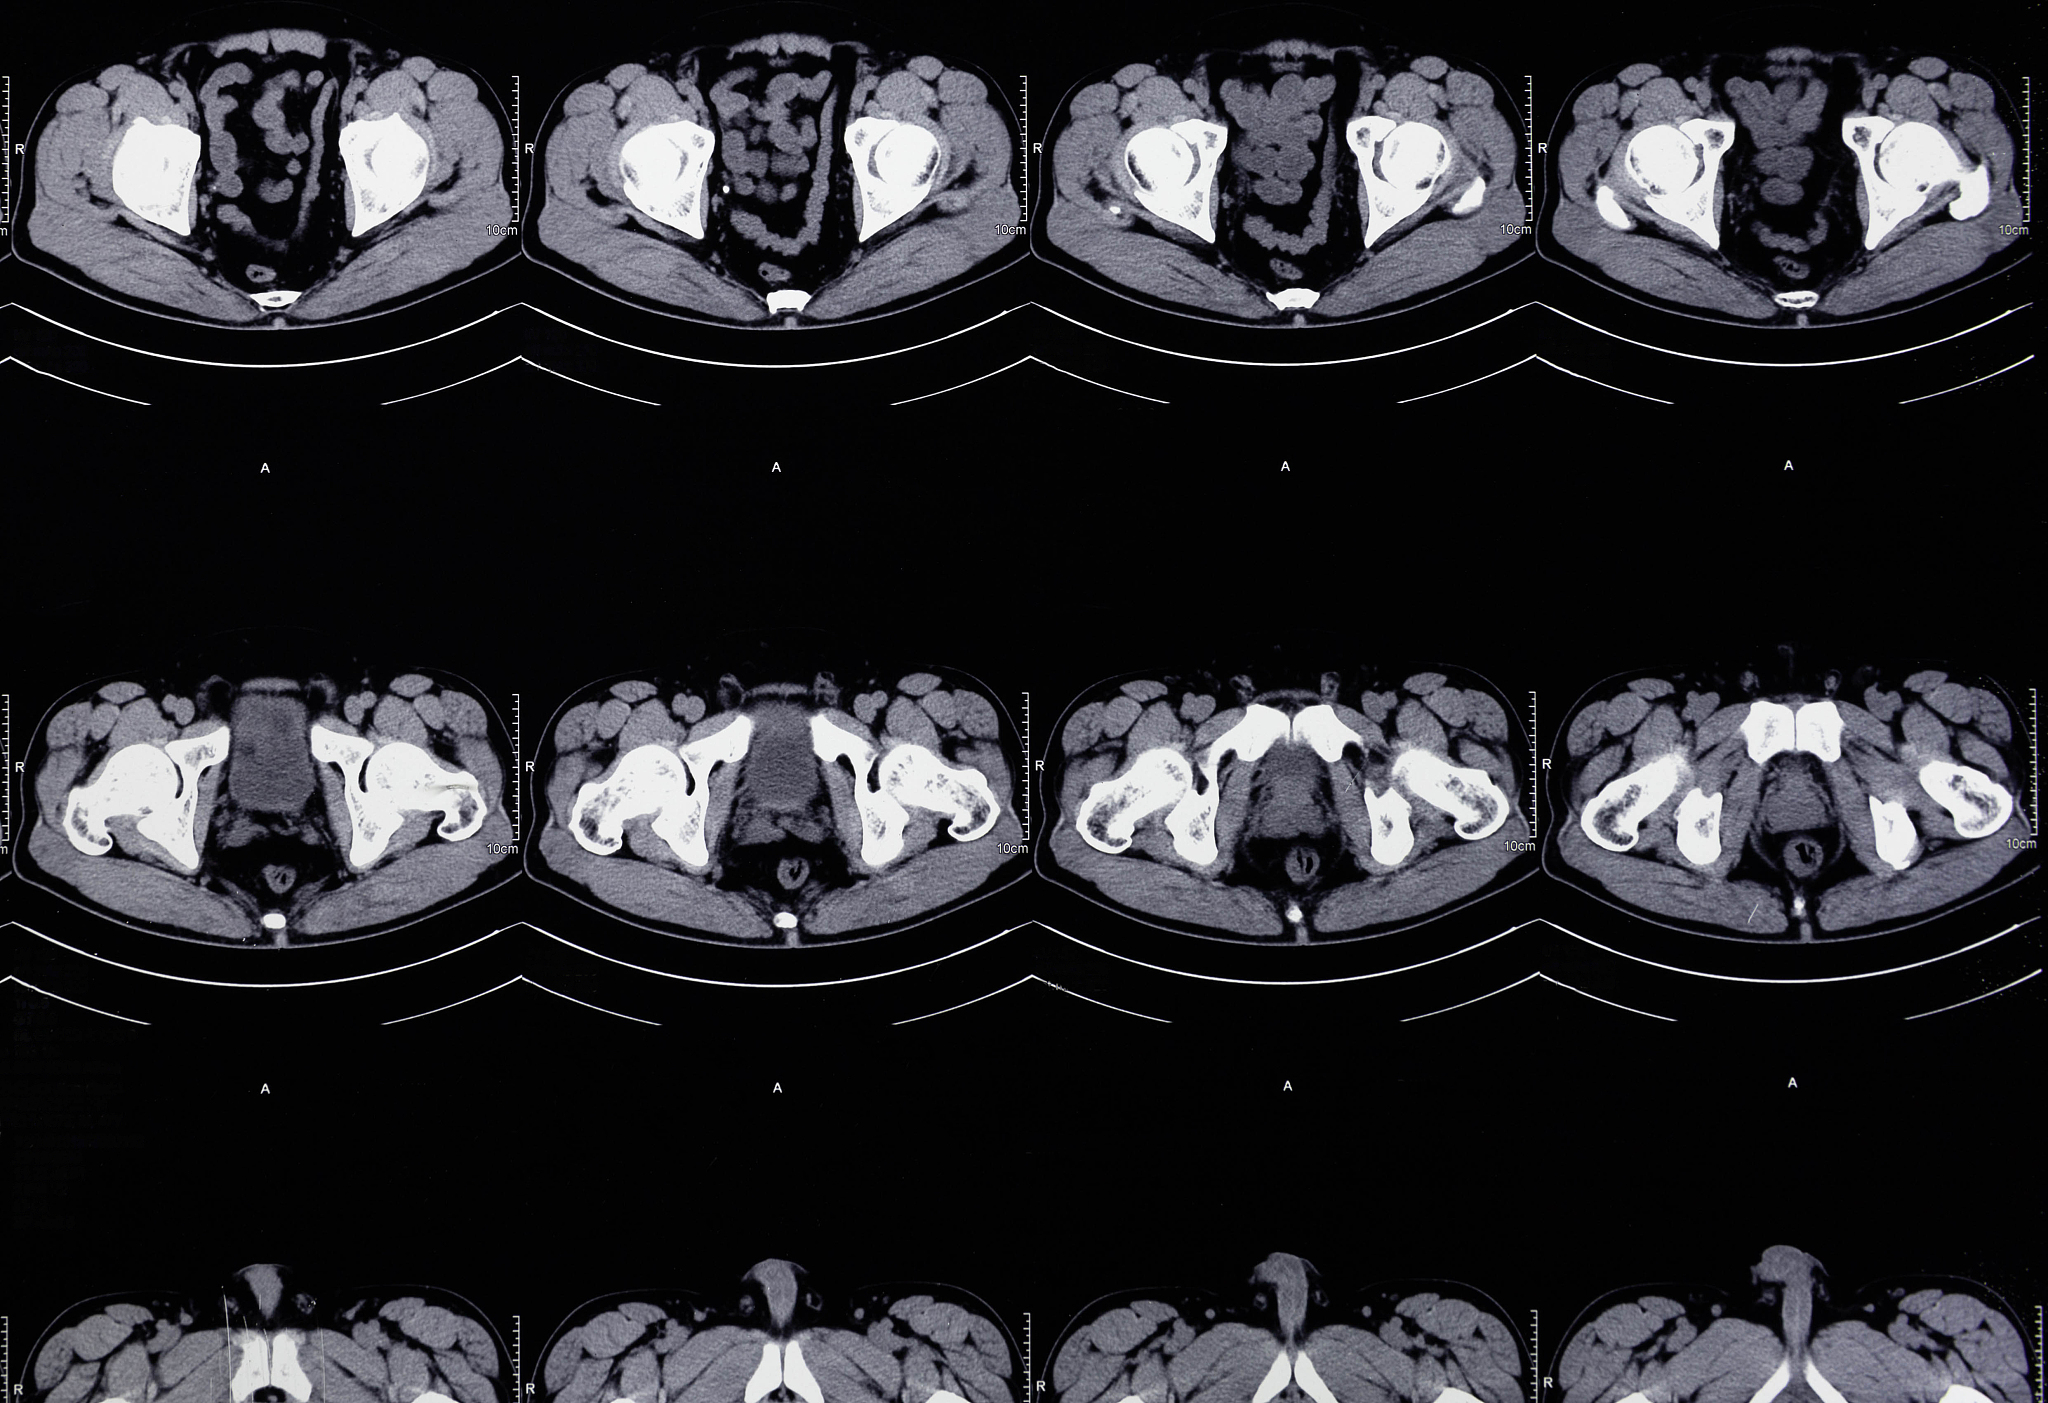

2. 腹部CT

腹部CT具有较高的空间分辨率和组织对比度,能够清晰地显示胆囊及其周围组织结构,在胆囊癌的分期和评估治疗效果方面具有独特优势。以下创新应用值得关注:

• 多层螺旋CT: 可以快速获取高质量的图像数据,提高诊断效率和准确性。* 螺旋CT增强扫描: 可以更好地显示肿瘤的血供情况,有助于判断肿瘤的良恶性和侵犯范围。* 螺旋CT三维重建技术: 可以重建胆囊及其周围血管的三维结构,为手术方案制定提供更直观的依据。